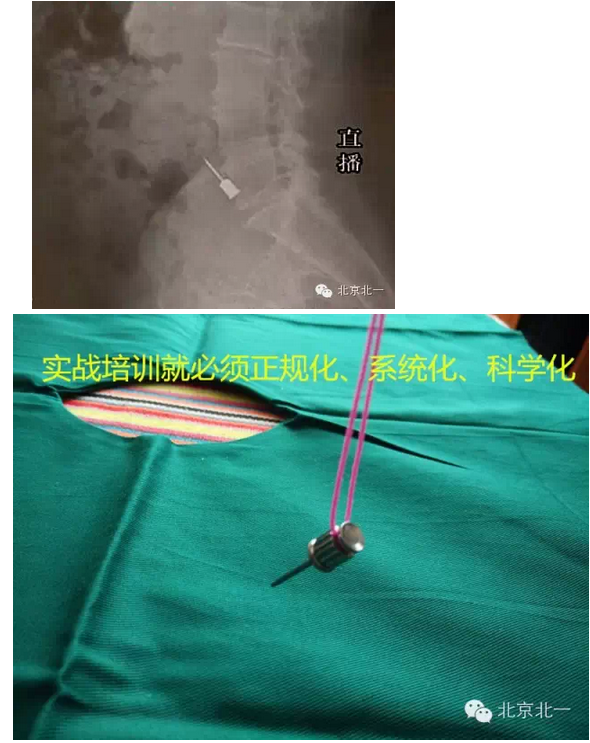

9關(guān)鍵一條,螺絲刀未纏線。容易誤吸或者誤吞(預(yù)防措施就是:在種植啟蒙教育階段強(qiáng)調(diào)栓繩子,實(shí)戰(zhàn)演練時(shí)就要形成良好習(xí)慣)

10關(guān)鍵第二條,強(qiáng)吸不到位,吸力不夠。(王老師認(rèn)為:強(qiáng)吸到位,手術(shù)就成功了一半)慢慢體會(huì)吧。

種植手術(shù)前實(shí)戰(zhàn)操作消毒鋪巾,打開(kāi)器械包,巡回護(hù)士為什么這么想伸手呢。